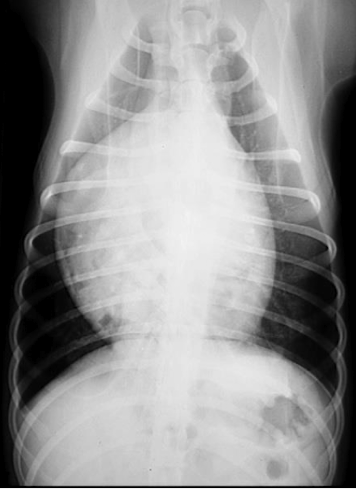

General condition?

Atelectasis

note the mediastinal/cardiac shift to the right and the soft tissue opacity of right middle lung lobe